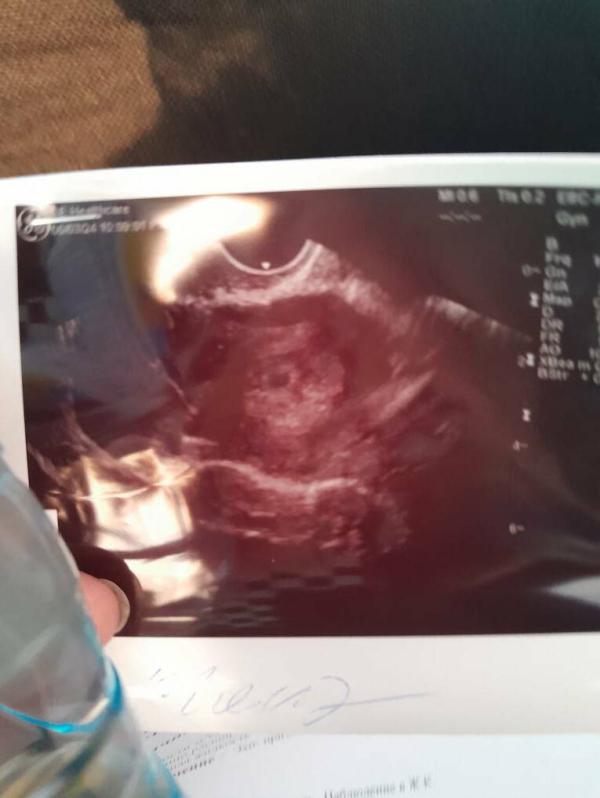

3 недельки

Еще с трудом пока верю😅

Это оно?да?

А тут сразу видно пя

@moms_nail я еще и врача переспрашивала,оно нет😂

Теперь через 2 недели на повторное